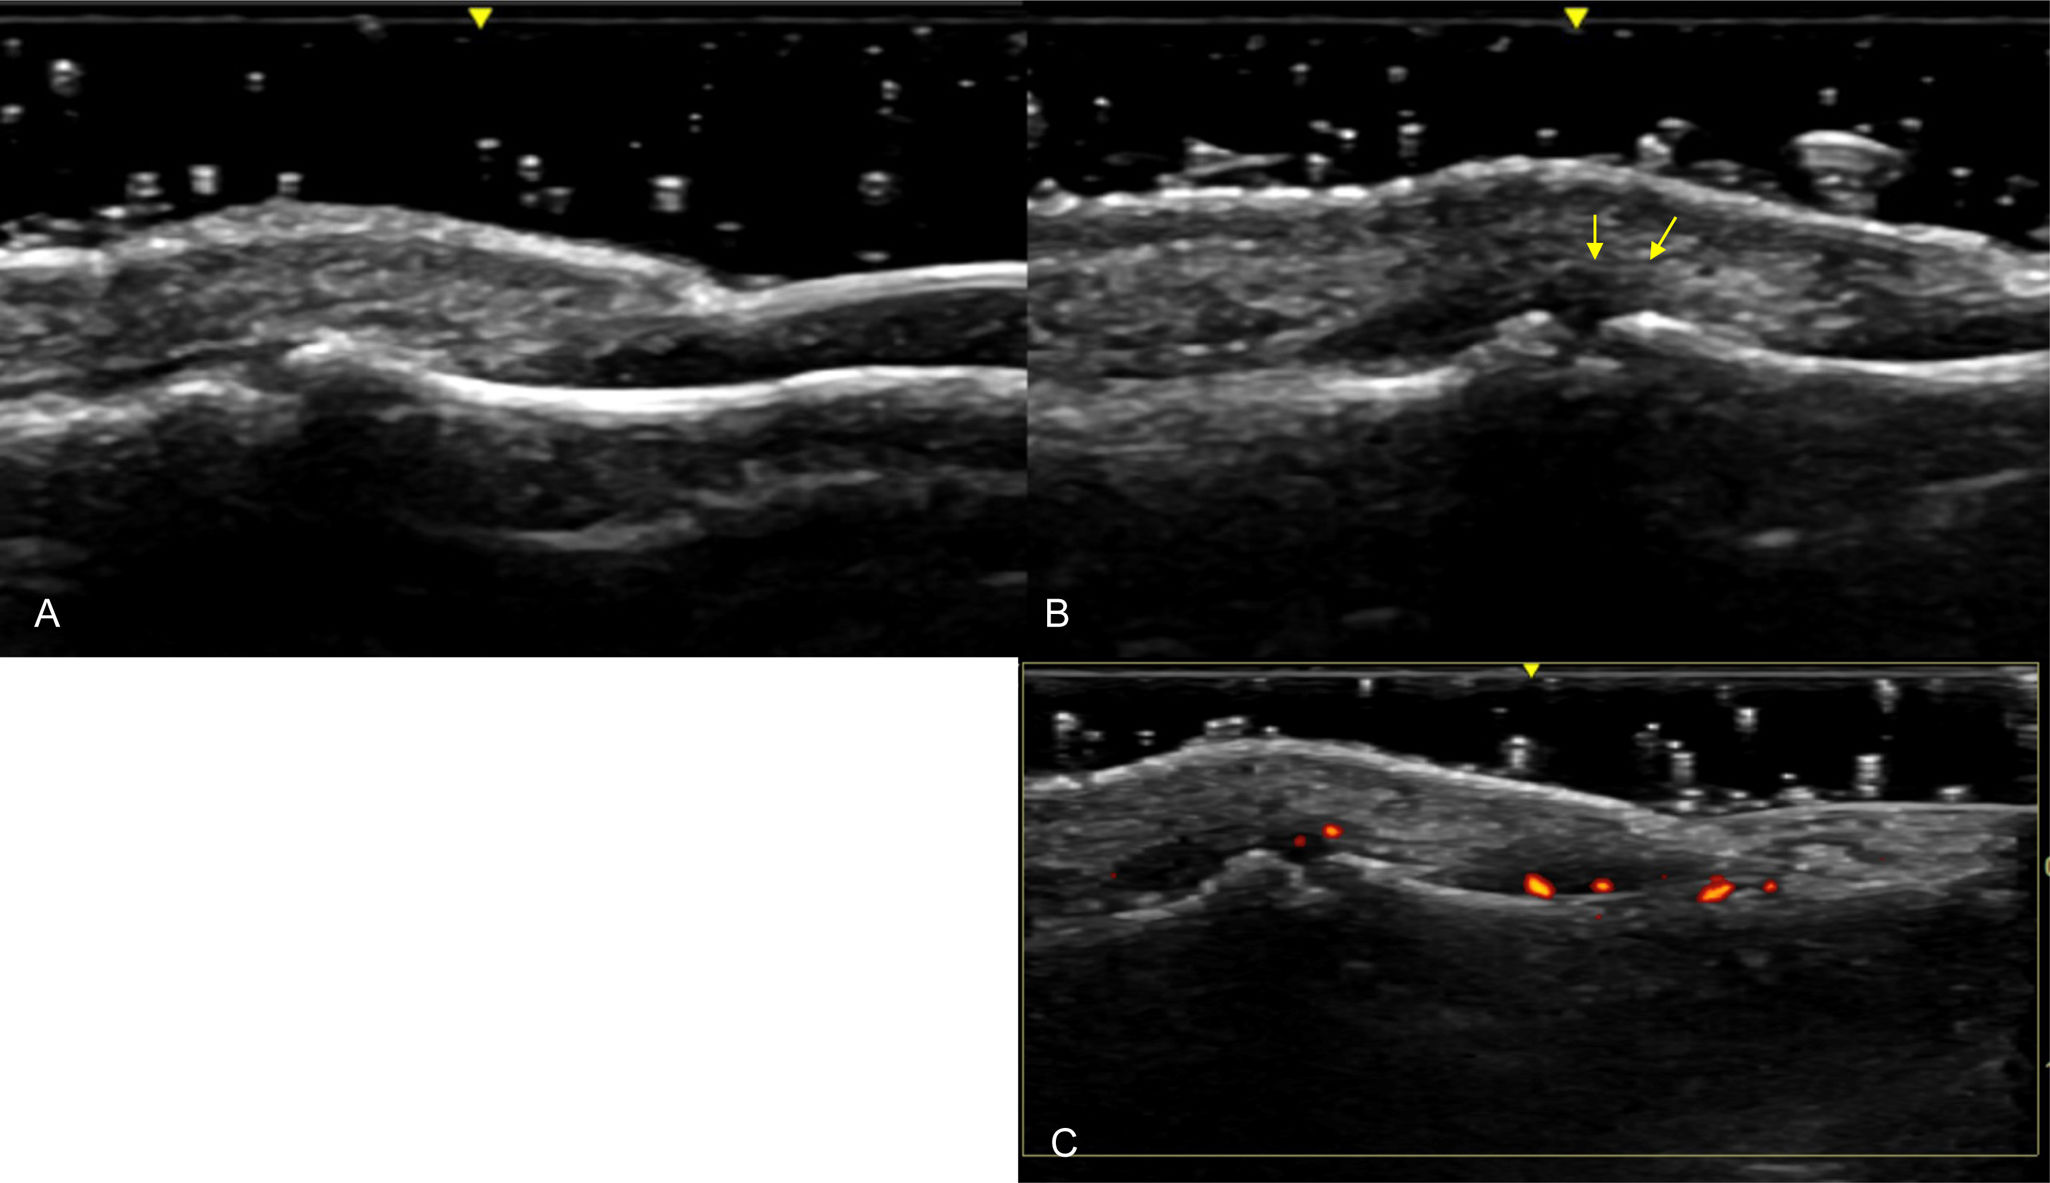

Furthermore, ultrasound reveals structural changes in the finger extensor tendons indicative of enthesitis, further demonstrating the utility of imaging in psoriatic arthritis evaluation (Fig. 8).

Fig. 8.Enthesitis at the Distal Insertion of the Extensor Tendon. Sonographic image obtained using Logiq e US system with an 8–18i MHz linear transducer. Comparative ultrasound images of the extensor tendon at the distal insertion in the same phalanx of both hands. One hand demonstrates significant thickening and hypoechogenicity indicative of enthesitis (B), while the other hand shows no such findings (A). Additionally, the presence of intra-tendinous power Doppler signal in the affected hand is noted as a sign of active enthesitis (C).